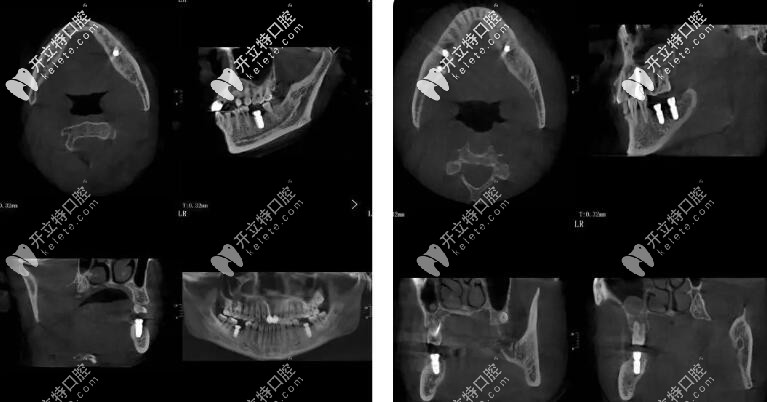

50歲的李先生,長期有不良的口腔習(xí)慣,導(dǎo)致全口牙齒大部分缺失, 現(xiàn)在的情況就是進(jìn)食困難、無法完成咀嚼,再后來顳下頜關(guān)節(jié)紊亂,去了不少醫(yī)院但是解決不了問題。

后來從朋友處打聽到朱院長,朱院長從抬高咬合到頜重建到塊狀骨移植,再從軟組織增量到美學(xué)塑形,解決了李先生的難題。

簡單的來說就是從吃飯咬不動(dòng)、嚼不碎再到咬合正常,并且恢復(fù)了全口的咀嚼功能。

種植牙手術(shù)